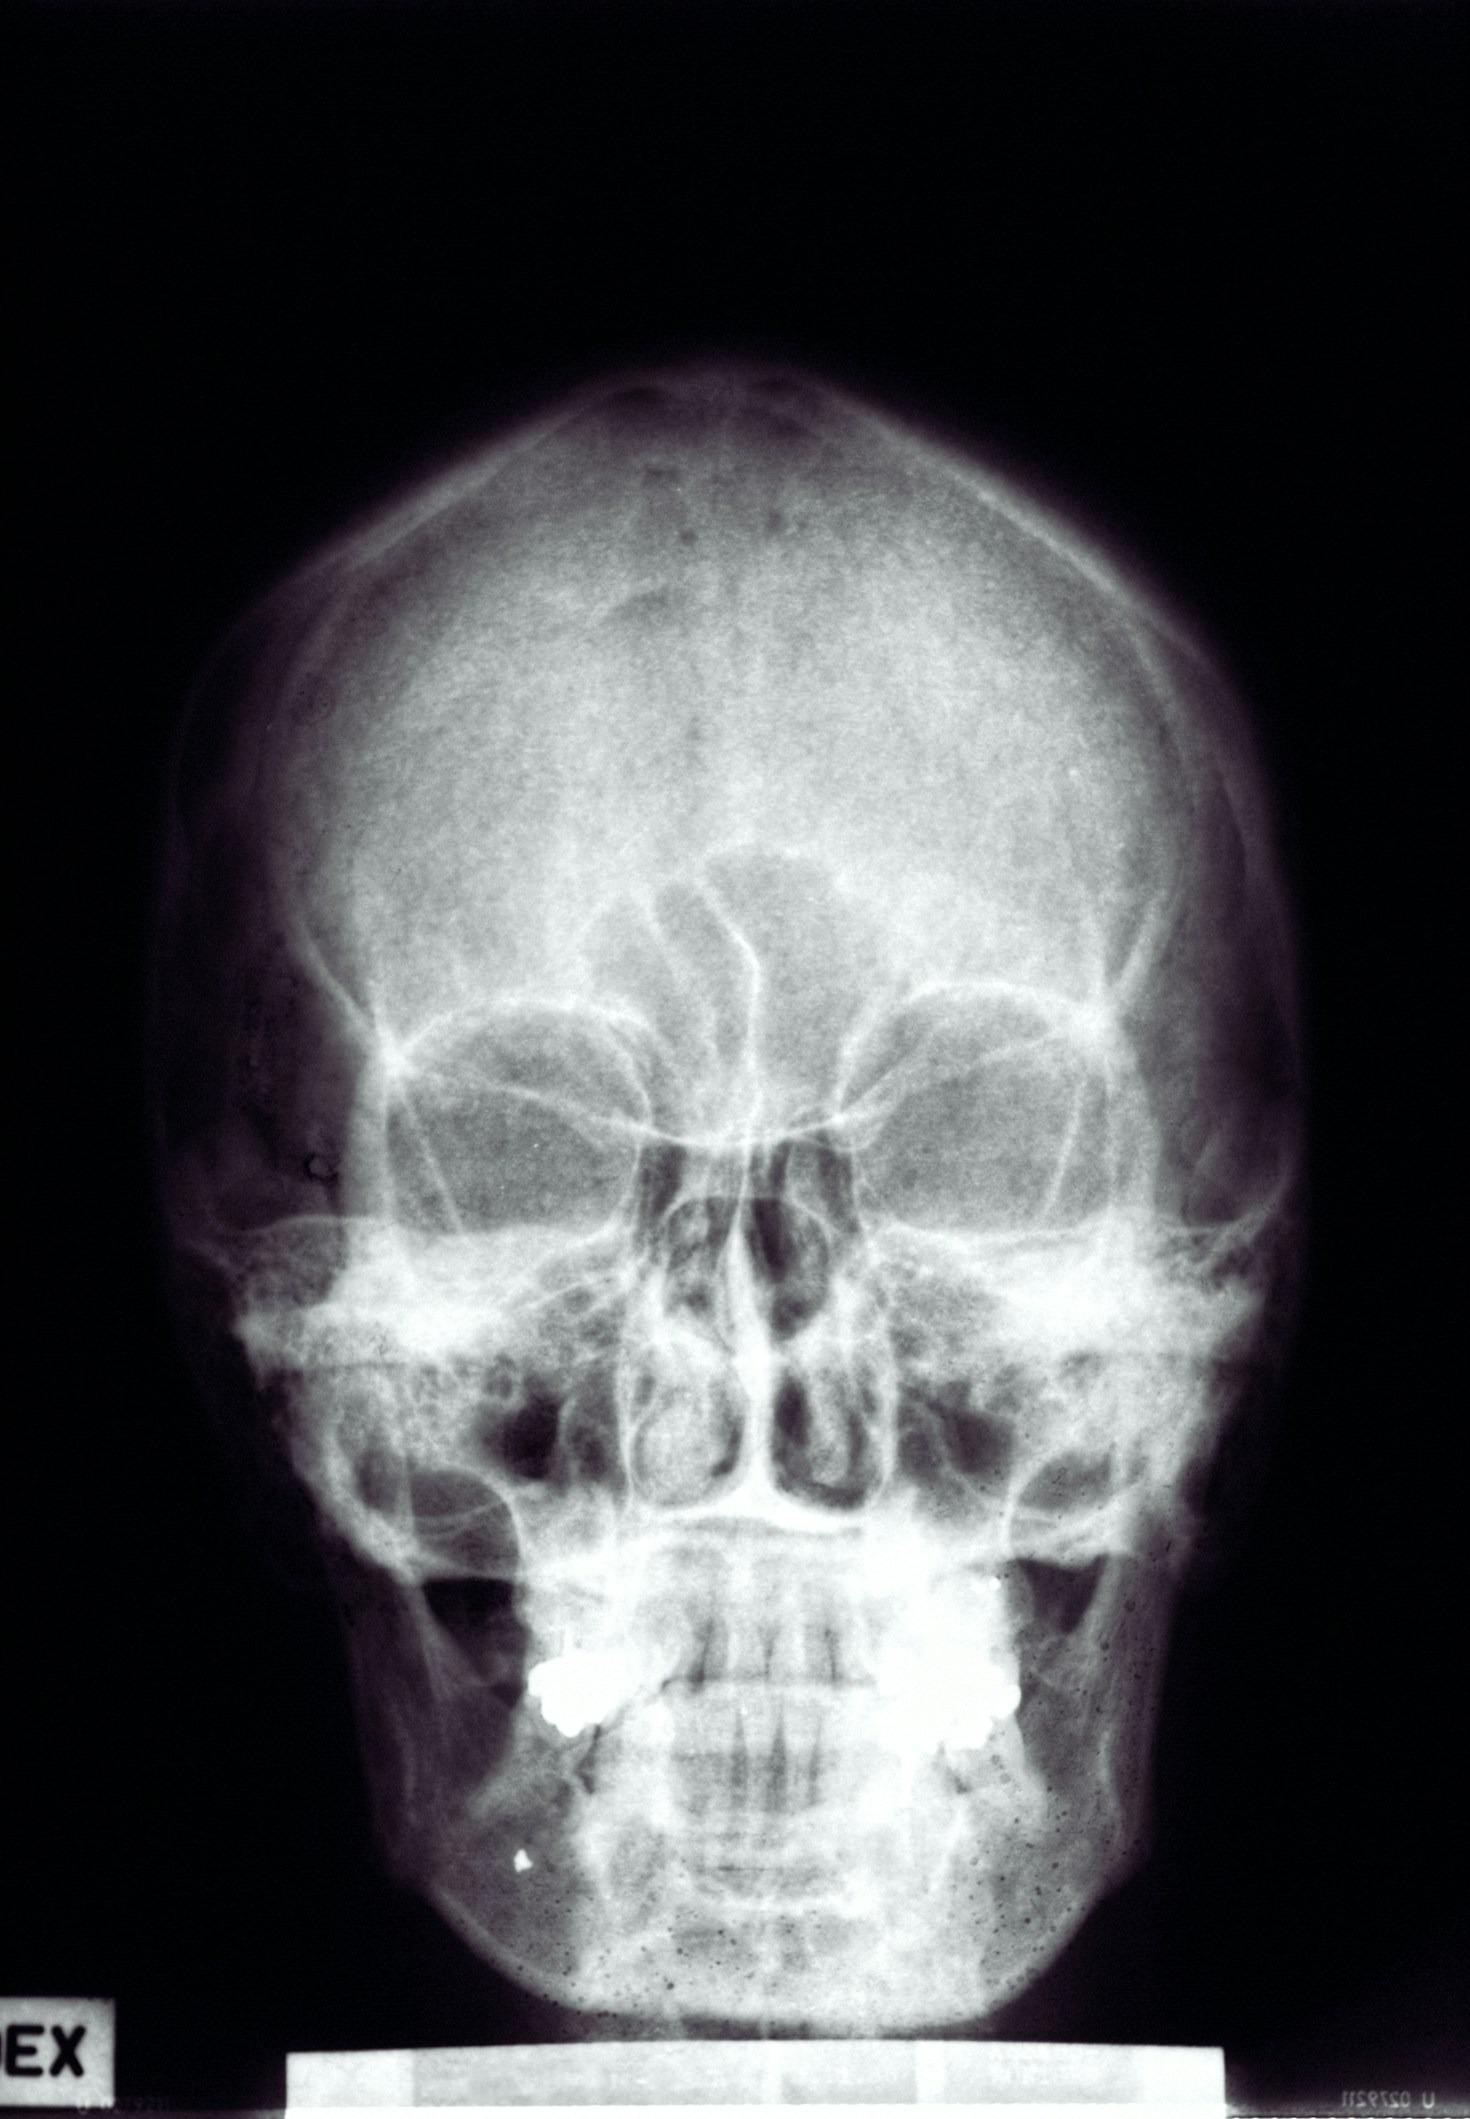

A área da radiologia está em constante evolução. Novas técnicas, novos equipamentos e o impacto da automação em todos os setores alicerçados pelo uso da inteligência artificial obriga os profissionais dessa área a estarem preparados para os desafios que se apresentam. Educação contínua é a palavra de ordem. Todo conhecimento atualizado é o que vai…